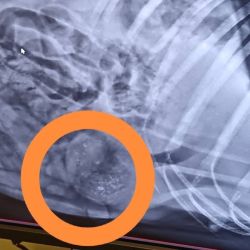

Anett hat uns heute über den aktuellen Gesundheitszustand von Mama Katica berichtet – leider mit überwiegend schlechten Nachrichten. Katica hat einen großen Weichteilbruch auf der linken Seite. Ihre Gesäugeleisten sind von kleinen Tumoren übersät.

In ihrem Bauch befinden sich Luftgewehrgeschosse.

Es wurden ein Bauchultraschall, Röntgenaufnahmen und Blutuntersuchungen durchgeführt – zum Glück waren alle Testergebnisse negativ. Der Ultraschall ergab zudem, dass sie kürzlich geworfen hat – ihre Gebärmutter ist noch offen.